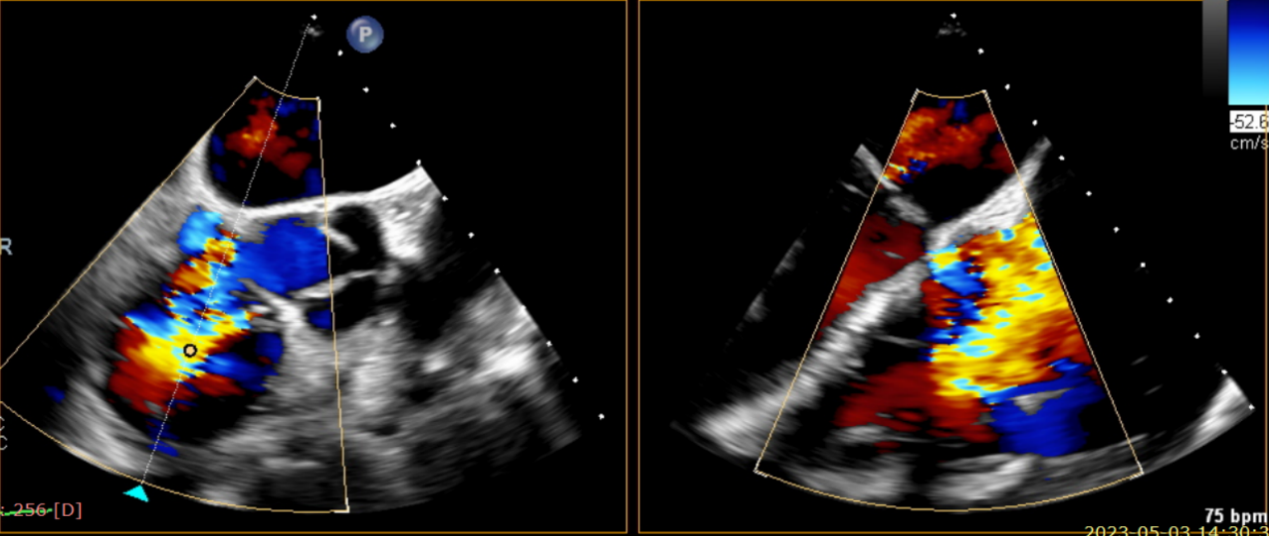

近日,美國紐約Montefiore醫(yī)學中心(Montrefiore Medical Center)的Azeem Latib教授團隊成功應用LuX-Valve Plus經(jīng)血管三尖瓣置換系統(tǒng)為兩位三尖瓣大量反流的患者完成三尖瓣置換手術。術后超聲顯示人工三尖瓣植入穩(wěn)定,瓣葉啟閉良好,僅殘余微量瓣周漏?;颊哂谑中g室即刻拔除氣管插管,血流動力學改善顯著。此次手術是LuX-Valve Plus于紐約的首次臨床應用,治療效果優(yōu)異。

術后Azeem Latib教授對LuX-Valve Plus經(jīng)血管三尖瓣置換系統(tǒng)的器械性能和治療效果大為稱贊,并且認為LuX-Valve Plus的手術體驗非常好。從治療效果來看,術后即刻超聲顯示三尖瓣反流幾乎完全消失,血流動力學改善顯著,患者恢復快。在面對復雜解剖結構、超聲影像質量不佳、有起搏導線干擾時,Lux-Valve Plus也體現(xiàn)了極強的適應性。Thomas Modine教授參與了術中指導,他同樣再次肯定了LuX-Valve Plus術中操作的便捷性,認為LuX-Valve Plus容錯率高,對術中影像的依賴小,并表達了后期希望可以更多地應用LuX-Valve Plus三尖瓣置換系統(tǒng)于臨床實踐,讓更多的三尖瓣重度反流患者盡早獲益,改善預后。